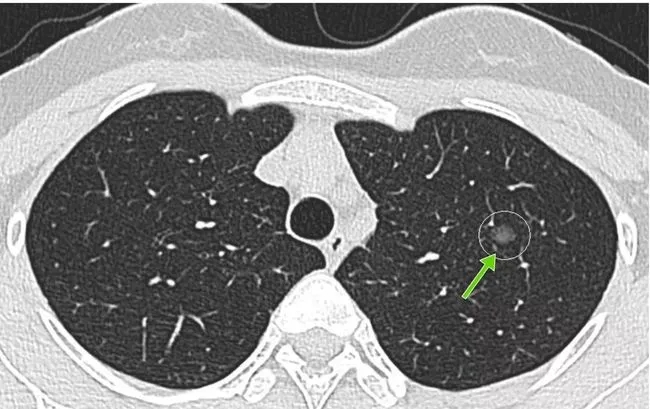

所謂的肺結(jié)節(jié),就是做胸部CT檢查時(shí)發(fā)現(xiàn)的肺部里密度增高的結(jié)節(jié)。

肺結(jié)節(jié)不是某種固定疾病的診斷,而是一個(gè)影像學(xué)上的定義。主要是指影像學(xué)表現(xiàn)為直徑≤3厘米的局灶性類圓形、密度增高的肺部陰影[1]。

(圖片來源于網(wǎng)絡(luò))